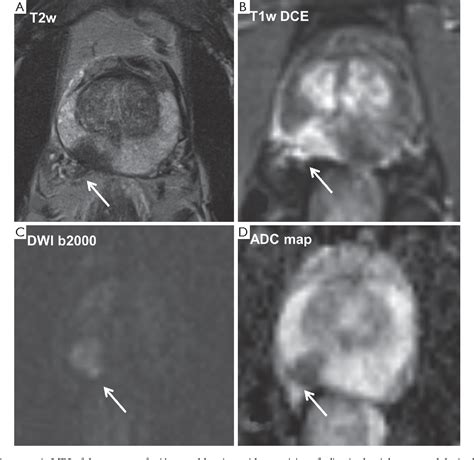

The diagnostic process typically involves three specific sequences that make up the "multi-parametric" aspect of the scan:

• T2-Weighted Imaging: Provides high-resolution anatomical details of the prostate structure.

• Diffusion-Weighted Imaging (DWI): Measures the movement of water molecules in the tissue, which is often restricted in malignant tumors.

• Dynamic Contrast-Enhanced (DCE) Imaging: Monitors how a contrast agent flows into the tissue, helping to highlight areas with abnormal blood vessel growth typical of cancer.

To standardize the interpretation of MRI results, radiologists utilize the Prostate Imaging-Reporting and Data System (PI-RADS). This scoring system ranges from 1 to 5, helping urologists determine the likelihood of clinically significant cancer:

• PI-RADS 1: Very low probability of significant cancer.

• PI-RADS 2: Low probability of significant cancer.

• PI-RADS 3: Intermediate probability; often requires further clinical correlation.

• PI-RADS 4: High probability of significant cancer.

• PI-RADS 5: Very high probability of significant cancer.

Understanding these scores is crucial for patients, as a PI-RADS 4 or 5 score will almost always lead to a recommendation for a biopsy to confirm the diagnosis and determine the appropriate course of treatment.